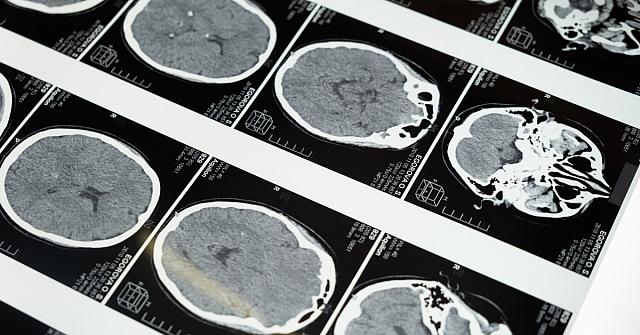

Μία ομάδα ερευνητών από το Πανεπιστήμιο Queen Mary του Λονδίνου ανέπτυξαν νέο τεστ που μπορεί να προβλέπει την εμφάνιση άνοιας έως και 9 χρόνια πριν τη διάγνωση. Σύμφωνα με τη δημοσίευση στο Nature Mental Health, η ακρίβεια της προγνωστικής τεχνικής ξεπερνά το 80%, εμφανίζοντας ισχυρό προβάδισμα έναντι παραδοσιακών μεθόδων όπως τα τεστ μνήμης και οι μετρήσεις συρρίκνωσης του εγκεφάλου.

Η ομάδα με επικεφαλής τον Δρ Charles Marshall, Καθηγητή, Honorary Consultant Νευρολογίας και επικεφαλής της ερευνητικής ομάδας του Κέντρου Προληπτικής Νευρολογίας στο Ινστιτούτο Πληθυσμιακής Υγείας Wolfson του Queen Mary, τα αποτελέσματα εξετάσεων fMRI (functional Magnetic Resonance Imaging = Λειτουργική Απεικόνιση Μαγνητικού Συντονισμού) σε περισσότερους από 1.100 συμμετέχοντες στη Βιοτράπεζα του Ηνωμένου Βασιλείου (UK Biobank), μια βάση δεδομένων γενετικών και ιατρικών πληροφοριών από μισό εκατομμύριο Βρετανούς.

Το fMRI είναι μια μέθοδος που επιτρέπει την απεικόνιση περιοχών του εγκεφάλου που ενεργοποιούνται σε συγκεκριμένα χρονικά διαστήματα. Στόχος της ομάδας ήταν να διερευνήσει πόσο αποτελεσματική ήταν η συνδεσιμότητα ανάμεσα στις δέκα περιοχές του εγκεφάλου που απαρτίζουν το δίκτυο αυτόματης λειτουργίας (Default Mode Network – DMN). Με βάση το μοτίβο συνδεσιμότητας στο συγκεκριμένο εγκεφαλικό δίκτυο, κάθε συμμετέχων έλαβε μια εκτίμηση για τον κίνδυνο άνοιας.